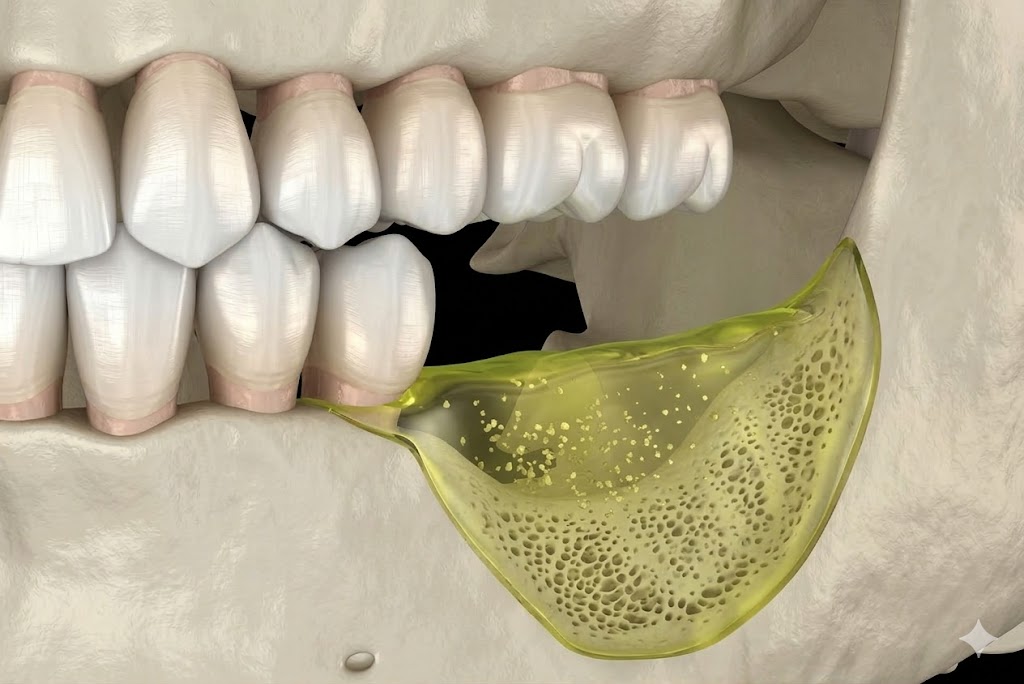

Recession exposes the tooth root, which has no enamel protection. This leads to sensitivity, especially to cold or sweet foods, and significantly increases the risk of root decay. Receded gum tissue does not grow back on its own — but it can be restored with a gum grafting procedure performed by a periodontist.

Early-stage gum disease (gingivitis) can often be managed with a professional cleaning and improved home care. More advanced disease may require scaling and root planing, surgical pocket reduction, or regenerative procedures. The sooner you come in, the more options are available — and the more of your natural teeth we can preserve.